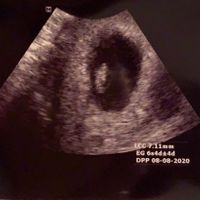

Sposine del mio cuore buongiorno e scusate l'ora ma non riesco ad aspettare....dopo quasi un anno di tentativi falliti e a -10 mesi dal matrimonio ecco il mio fagiolino ♥️♥️♥️ Le emozioni sono strane...